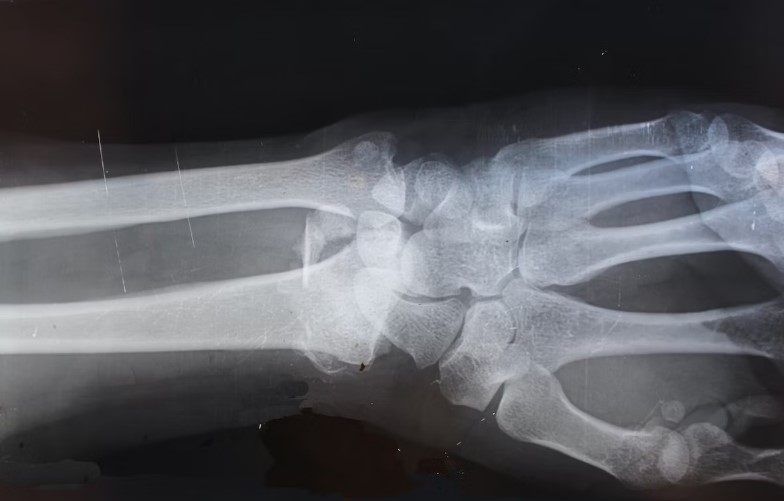

오늘은 류마티스 관절염 치료법에 대해 더 깊게 알아보려 합니다. 류마티스 관절염은 현재 완치할 수 있는 치료법이 없지만, 적절한 치료와 관리를 통해 증상을 통제하고, 관절의 손상을 최소화하며, 생활의 질을 유지할 수 있습니다.

수술: 약물 치료, 물리 치료, 운동 치료 등의 보존적 치료에도 불구하고 관절의 손상이 진행되거나 증상이 심각한 경우에는 수술을 고려할 수 있습니다. 관절 치환술은 손상된 관절을 인공 관절로 교체하는 수술로, 류마티스 관절염 환자들에게 새로운 생활의 질을 선사할 수 있습니다.

결론적으로, 류마티스 관절염의 치료는 개별 환자의 상태와 필요에 따라 맞춤화되어야 합니다. 통증과 염증을 관리하고, 관절의 손상을 최소화하며, 생활의 질을 유지하는 것이 치료의 주요 목표입니다. 그러므로, 류마티스 관절염 증상을 겪고 있다면, 즉시 의료 기관에 방문하여 전문가의 도움을 받아야 합니다.